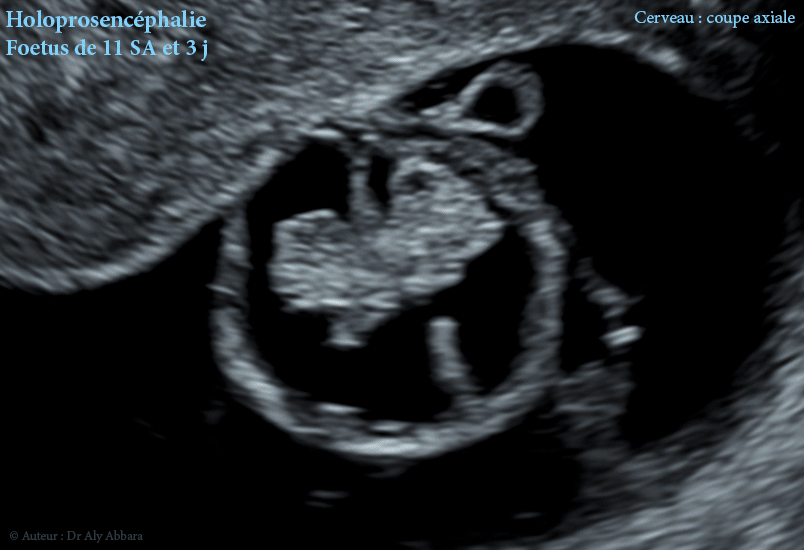

Séquences échographiques montrant, chez un fœtus de 11 SA et 3 jours (LCC = 48 mm), la présence d'une holoprosencéphalie d'après les éléments malformatifis suivants :

• La discontinuité de la cloison interhémisphérique dans sa partie moyenne et une large communication entre les deux ventricules latéraux

• la fusion, à travers de cette discontinuité, des deux plexus choroïdes sur la ligne médiane d'où l'absence du "signe du papillon" que les plexus choroïdes dessinent habituellement dans le cerveau fœtal normal à cette âge de grossesse.

• Au cours du premier trimestre de la grossesse, entre 11 et 14 SA, les deux plexus choroïdes normaux occupent largement les deux ventricules latéraux et composent ensemble une forme ressemblant à un papillon "signe du papillon - Butterfly sign" ; ce signe est absent dans l'holoprosencéphalie alobaire.

• En cas d'holoprosencéphalie alobaire, on peut observer la présence d'un ventricule unique au lieu des deux ventricules latéraux du cerveau, puis l'apparence anormale des plexus choroïdes : absence du " signe du papillon "